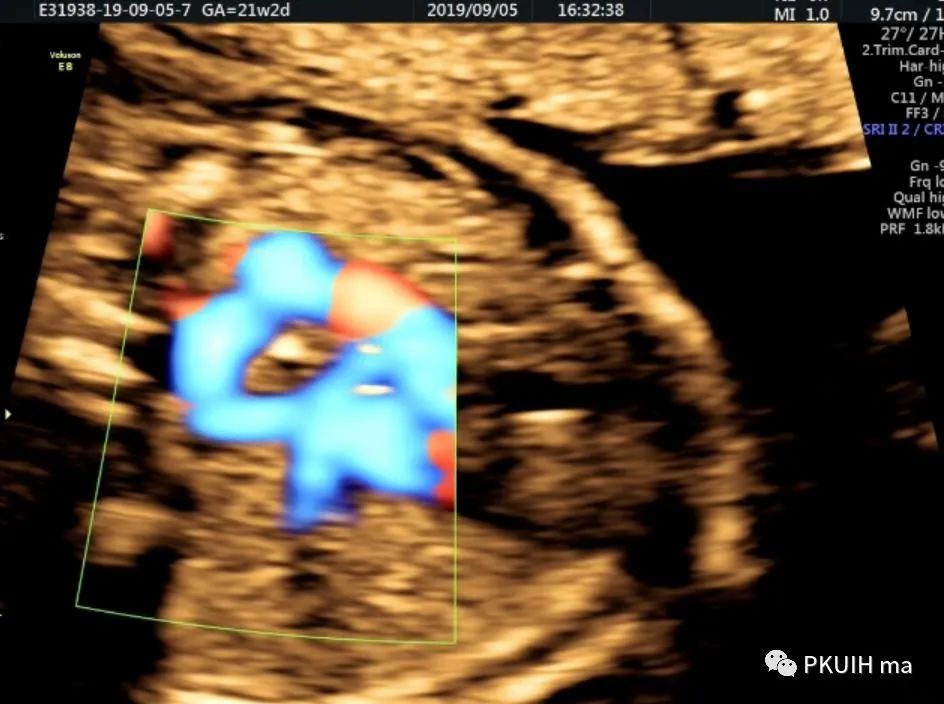

下面几张图都是右位主动脉弓、左动脉导管合并左锁骨下动脉迷走的病例,患儿出生后随访均无明显临床症状

主动脉弓走行于气管的右侧,与左位的动脉导管形成“U”型环(不完全血管环),包绕气管和食管。主动脉冠状切面可见左锁骨下动脉起自于主动脉弓降部,向左肩部走行。